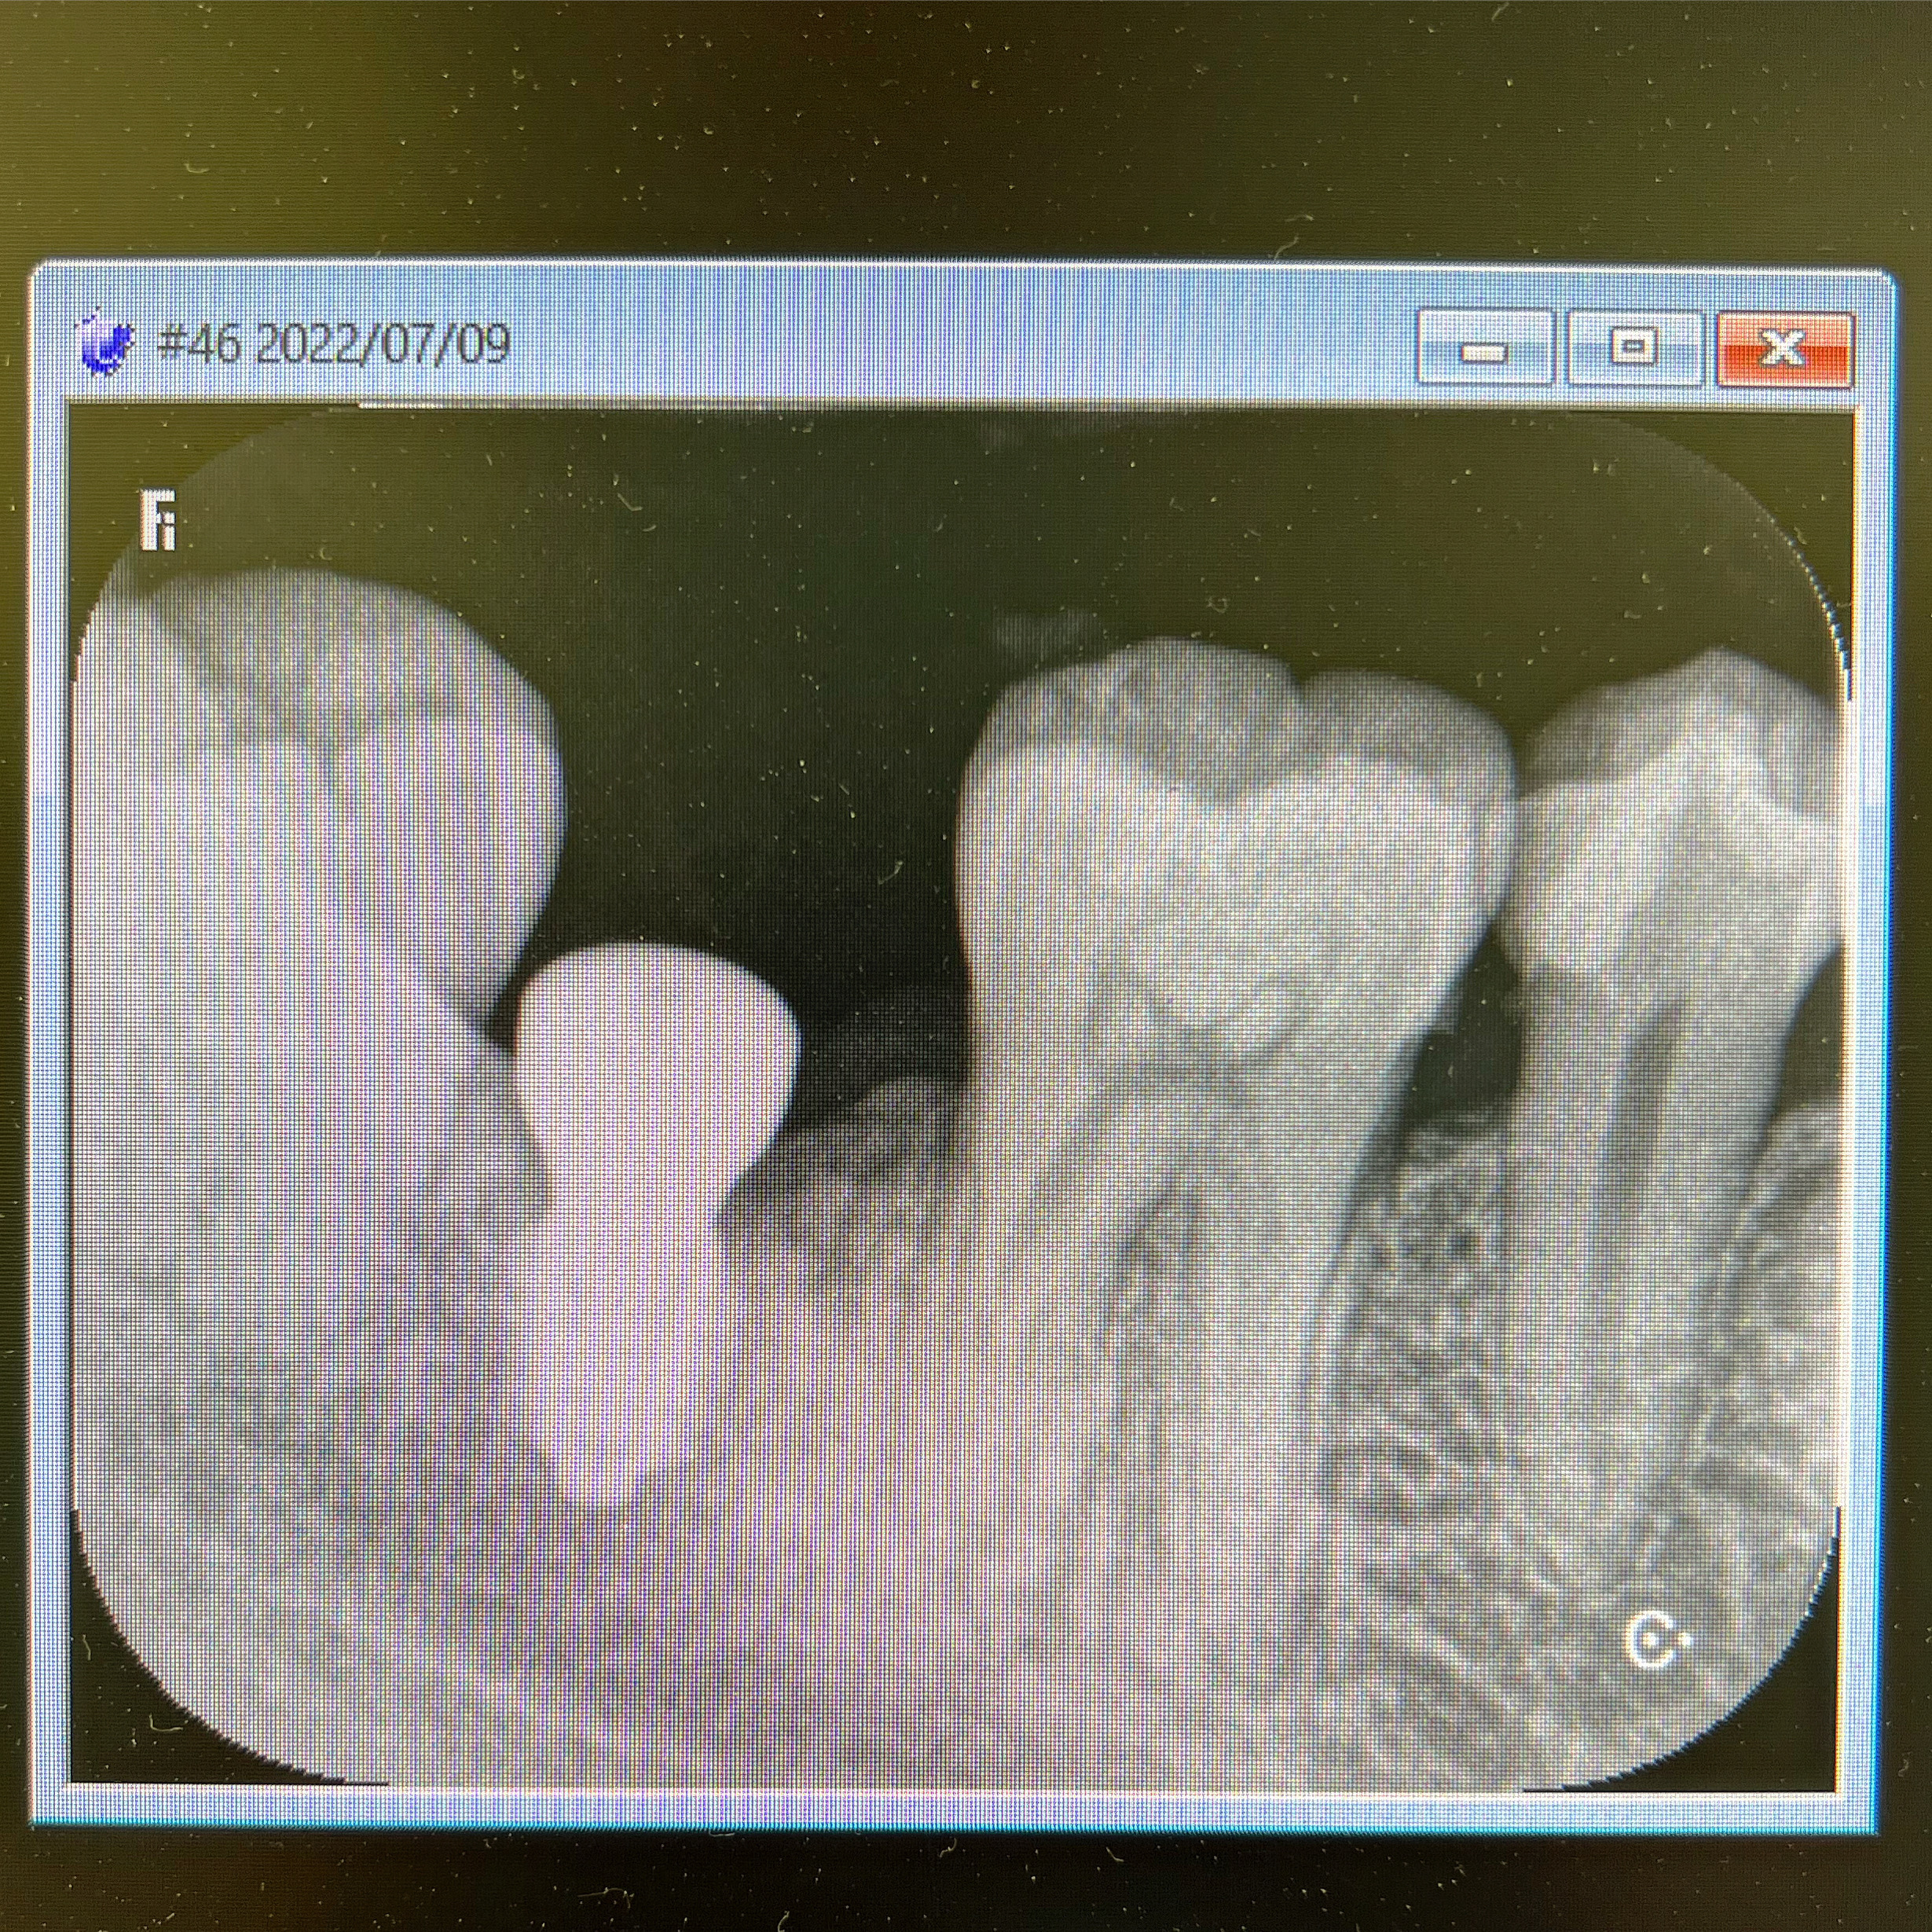

インプラントのため抜歯?いやいや、歯を引っ張り出せばまだ使える!

2023/01/20症例